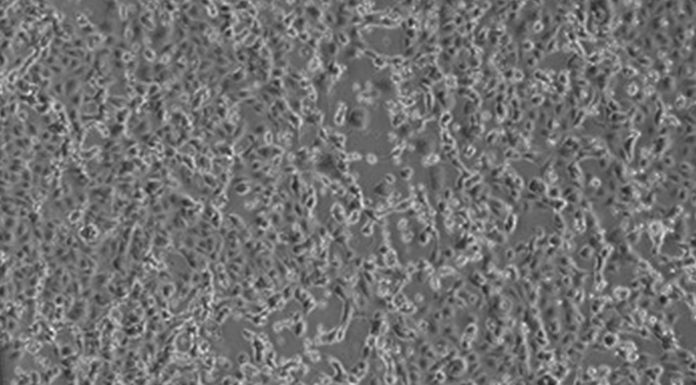

ROMA (ITALPRESS) - Sono stabili "con parametri emodinamici invariati" le condizioni cliniche dei coniugi cinesi ricoverati nella terapia intensiva dell'Istituto Spallanzani di Roma perchè positivi al Coronavirus. "Continuano terapia antivirale e la prognosi resta riservata", fa sapere l'ospedale. Sono...